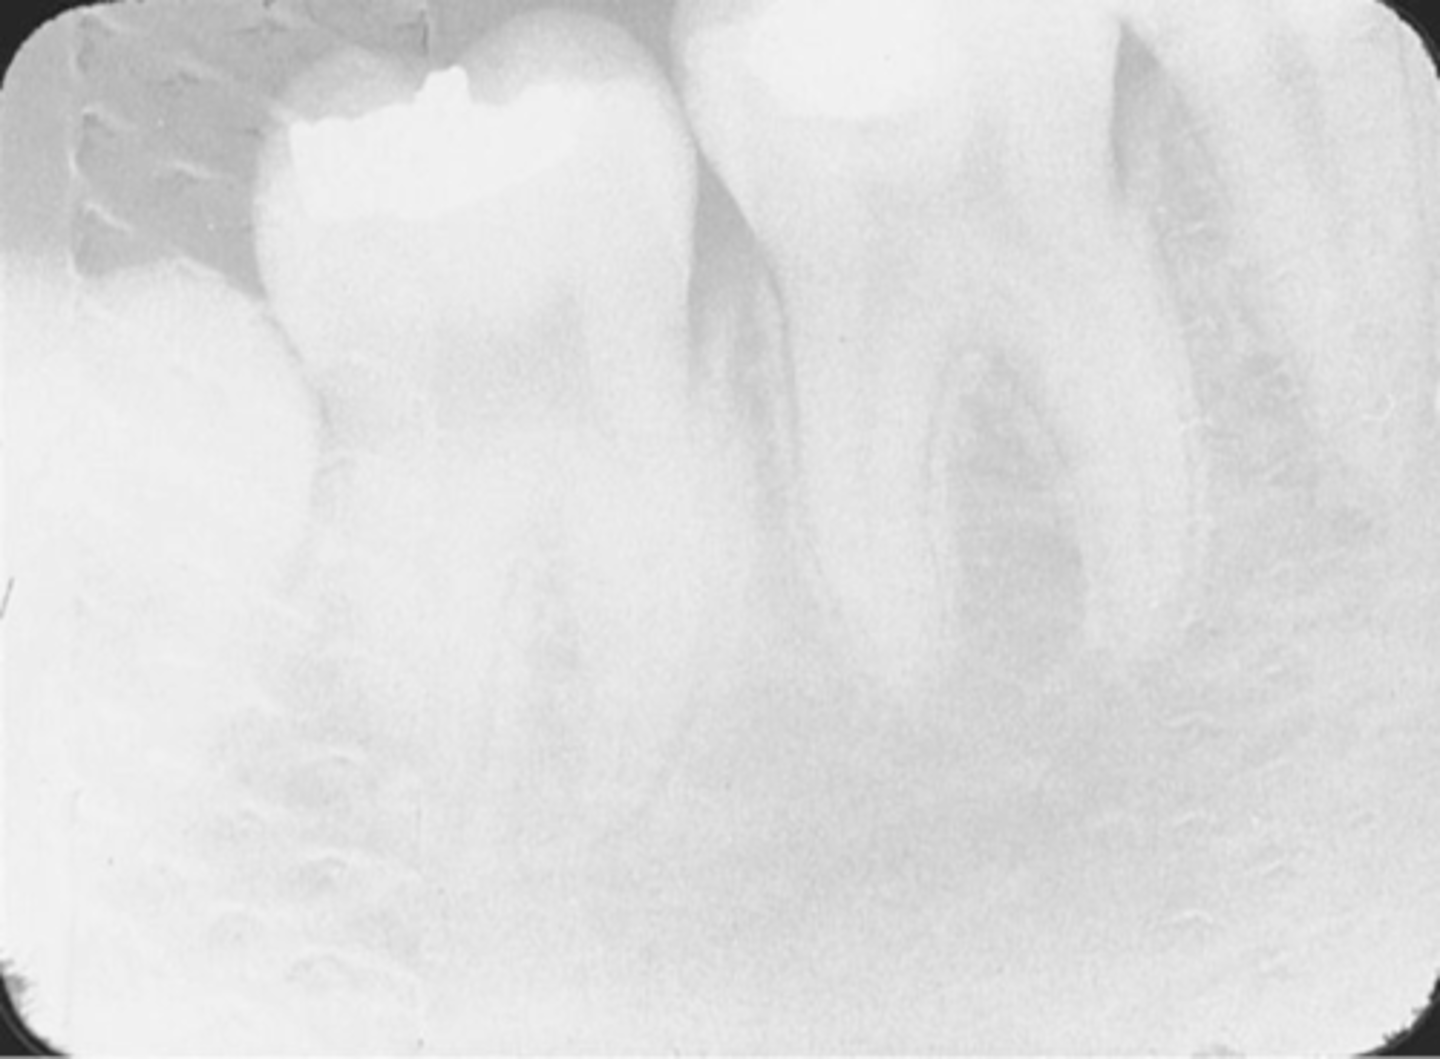

Incorrect Vertical Angulation-->Foreshortened Images

-Teeth appear short with blunted roots

-Vertical angulation was excessive, or too steep, resulting in images that are shorter than the actual teeth

-This occurs more often with the bisecting technique

-To prevent do not use excessive vertical angulation

Tube Head & PID-->Foreshortening of the image

-Excessive angulation (too steep) causing shortening of the anatomy of the teeth and/or cutting off occlusal or incisal edge.

1. PID Too steep Vertical angulation

2. Foreshortening of the image: Excessive angulation (Too Steep)

Foreshortened image; Vertical angulation is too steep, Possible deflected film.